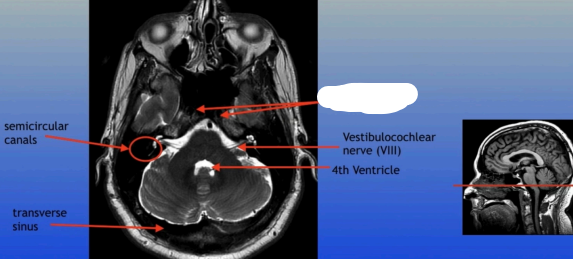

Semicircular Canals

Transverse Sinus

Vestibulocochlear Nerve (VIII)

4th Ventricle